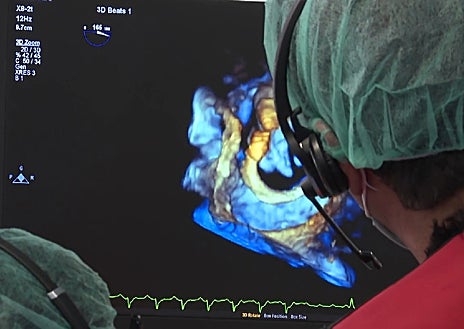

La intervención se realiza de forma mínimamente invasiva, accediendo al corazón a través de la ingle, lo que evita tener que abrir el pecho del paciente. Gracias a una técnica de imagen muy precisa llamada ecocardiografía transesofágica, los médicos pueden ver con detalle la zona de la válvula mitral y controlar con gran exactitud la colocación del dispositivo, aumentando así la seguridad y la eficacia del procedimiento.

El tratamiento consiste en introducir un catéter que coloca primero un anillo alrededor de la válvula mitral dañada, creando una base firme. Sobre ese anillo se implanta después una válvula biológica expansible que sustituye a la original y permite que la sangre vuelva a fluir correctamente por el corazón.